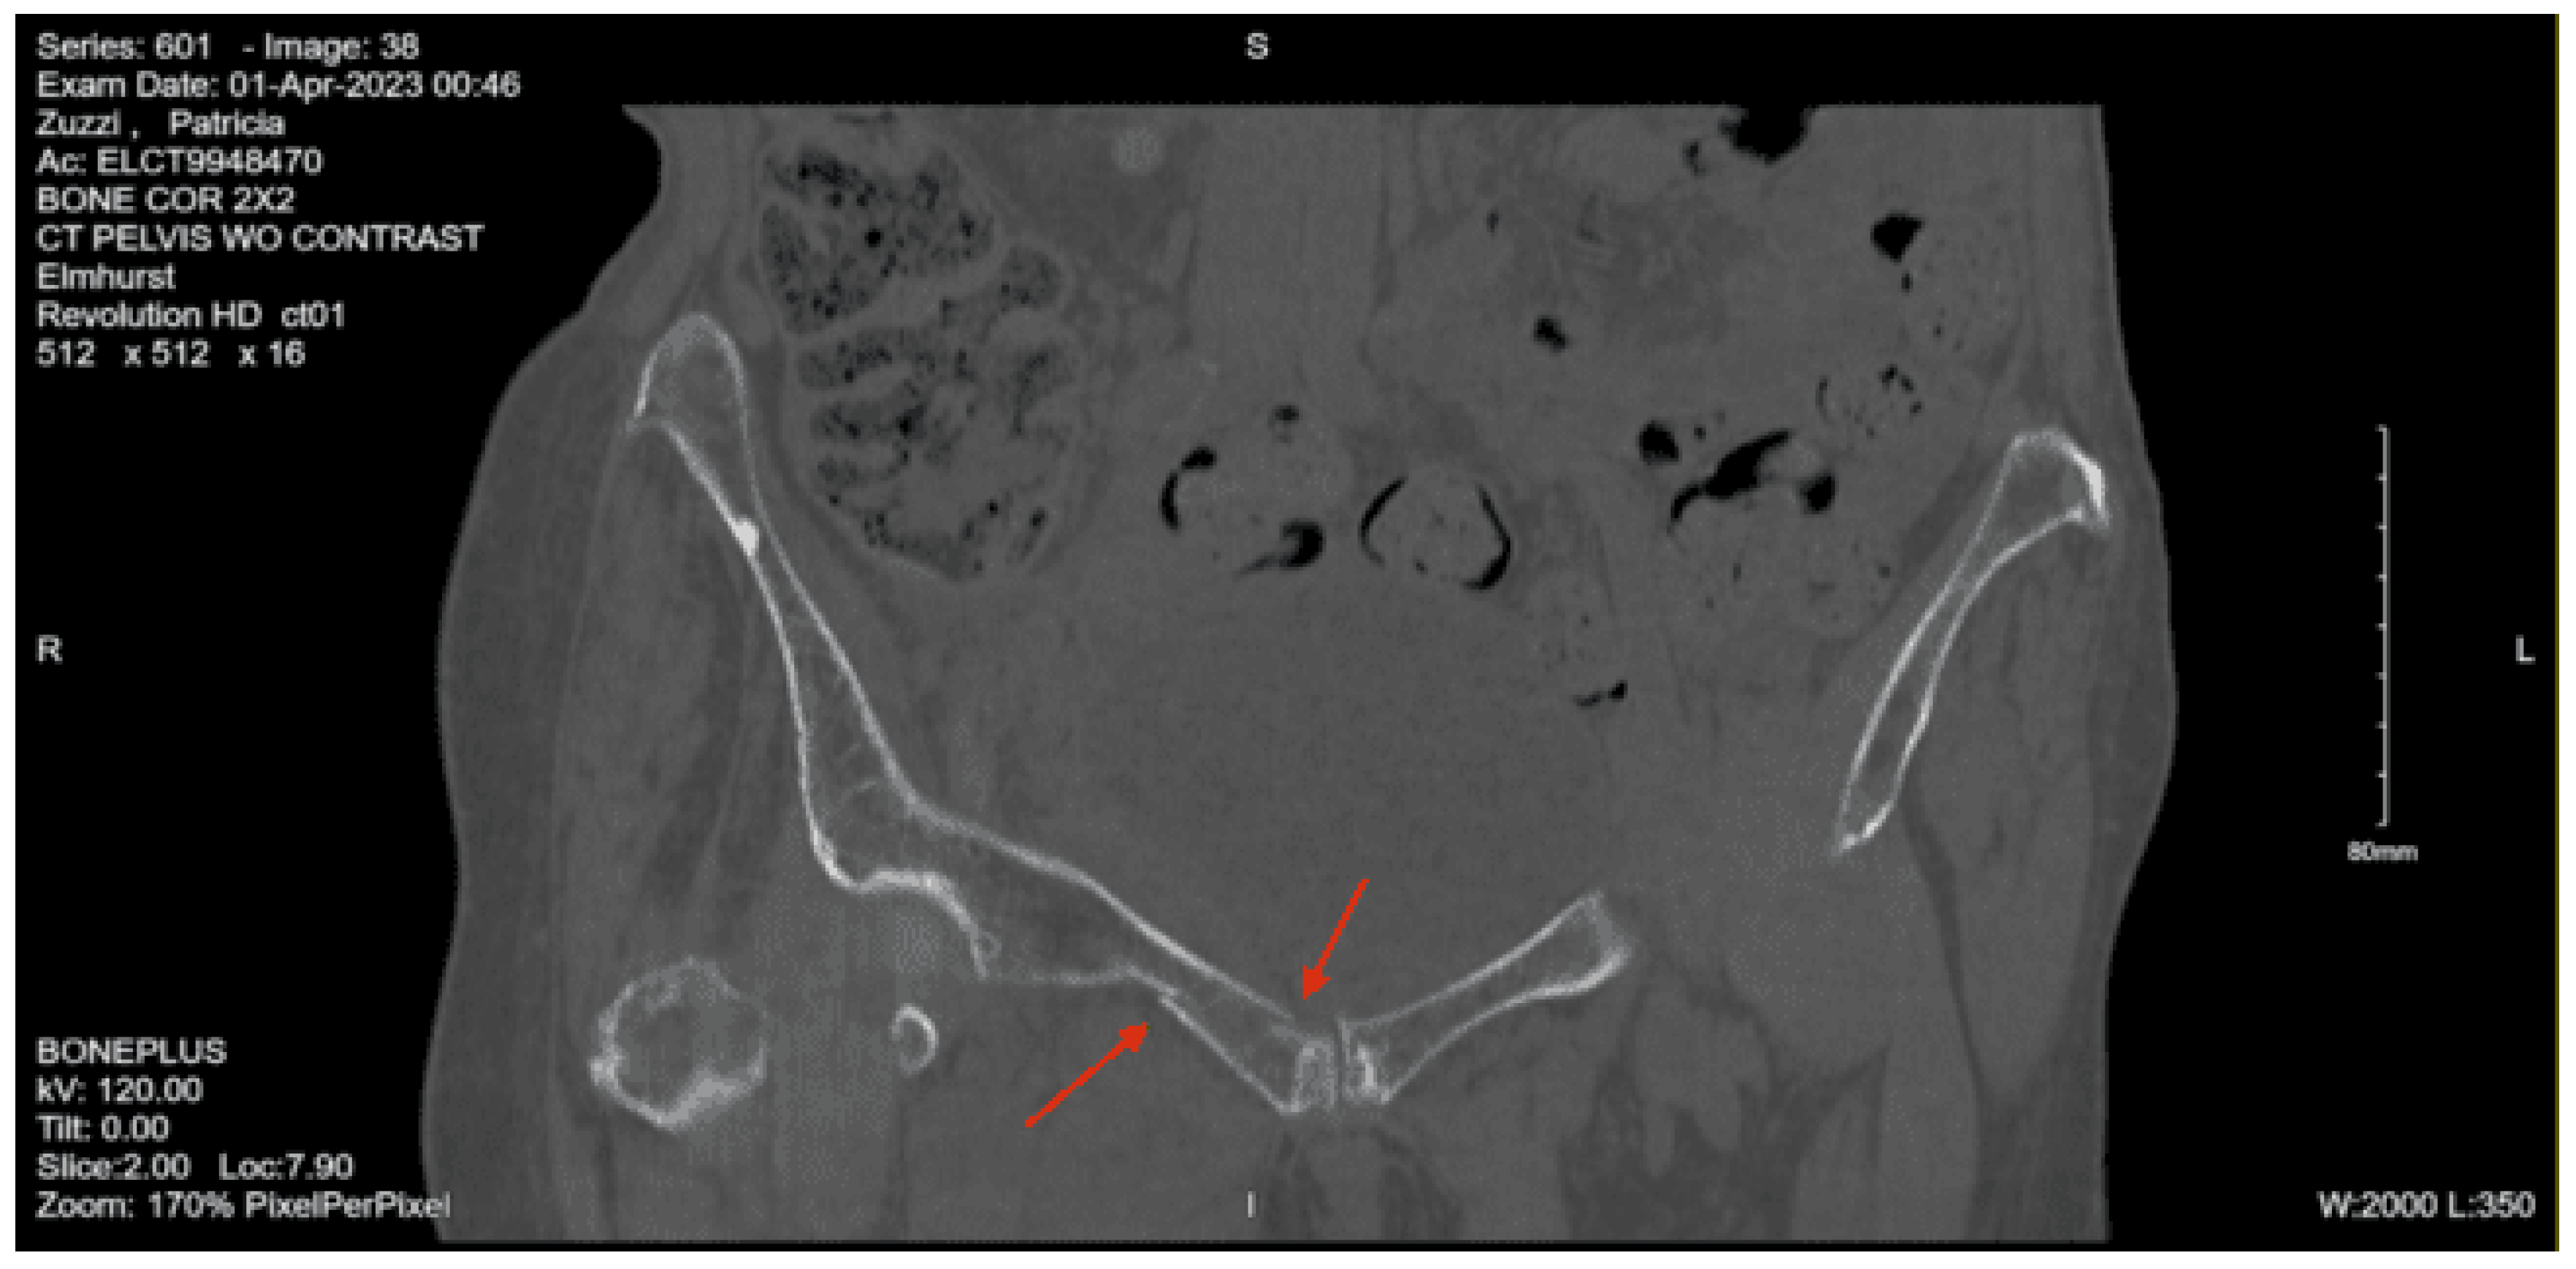

Imaging as shown in Figure 37, Figure 38, Figure 39, Figure 40 and Figure 41:

CT lumbar spine non-contrast: Nondisplaced right sacral ala fracture

CT abdomen pelvis with contrast: No evidence of solid abdominal organ injury is seen. There are right superior and inferior rami fractures, and adjacent pelvic muscular enlargement likely secondary to intramuscular hematoma. There is a right pubic symphysis fracture with adjacent hematoma.